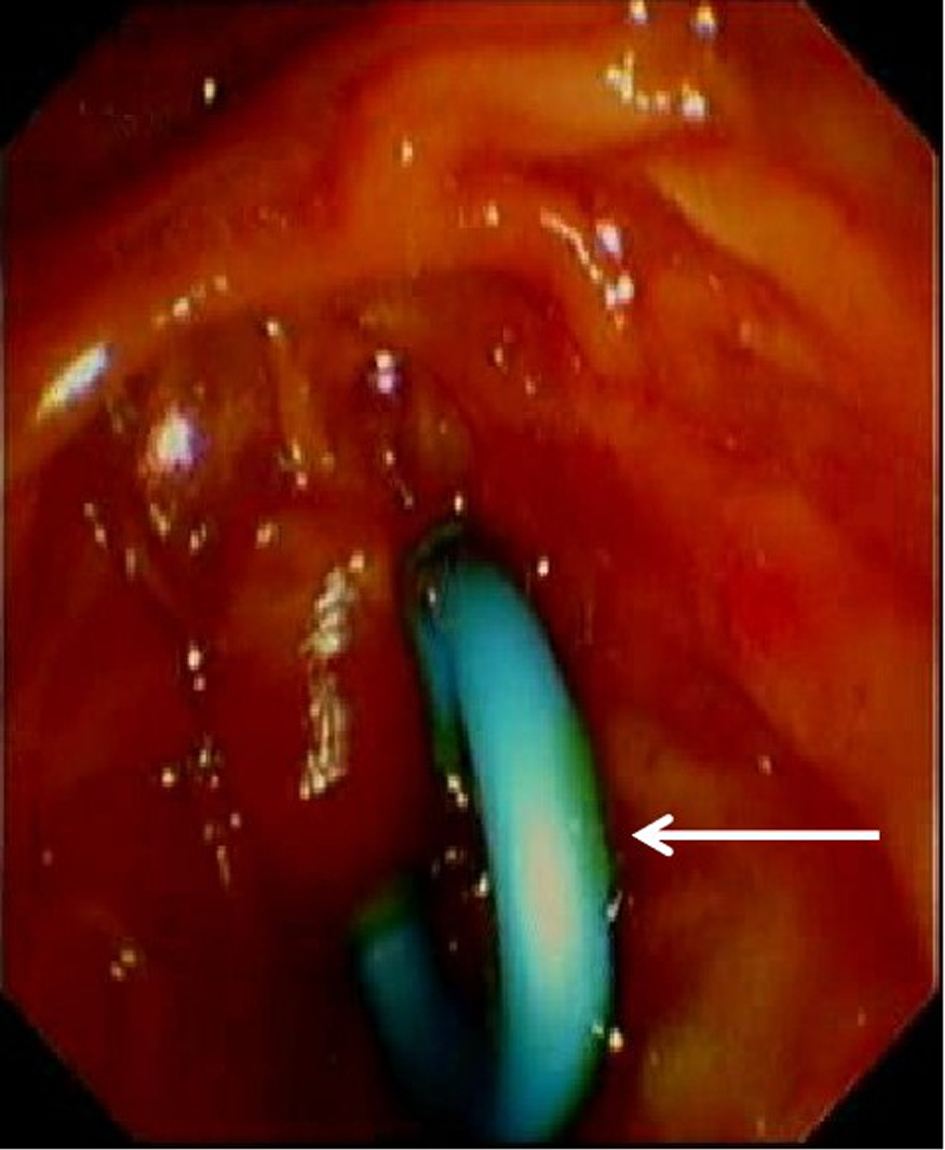

Safety and efficacy of modified pancreatic duct stent in biliary drainage after complete bile duct stone removal by endoscopic retrograde cholangiopancreatography

Jialin LI, Likun REN, Xun RAN, Shaoxuan XIA, Yutong ZHOU, Xin HUANG, Min HAN

2023, 39(8): 1911-1918. DOI: 10.3969/j.issn.1001-5256.2023.08.021

Abstract(1519) HTML (652) PDF (2008KB)(68)

Abstract:

Objective  To investigate the clinical application value of modified 7Fr pancreatic duct plastic stent in biliary drainage.  Methods  Clinical data were collected from 121 patients with choledocholithiasis who underwent endoscopic retrograde cholangiopancreatography (ERCP) lithotomy and biliary drainage in Department of Hepatobiliary Surgery, The Affiliated Hospital of Guizhou Medical University, from April 2021 to June 2022, and according to the method for postoperative biliary drainage, they were divided into modified stent group with 59 patients and nasobiliary drainage group with 60 patients. The patients in the modified stent group received drainage with the modified 7Fr pancreatic duct plastic stent, and those in the nasobiliary drainage group received nasobiliary drainage. A retrospective analysis was performed for their clinical data, and stent dislodgement was observed for the modified stent group. The two groups were compared in terms of clinical outcome, postoperative comfort, and postoperative complications. The independent-samples t test was used for comparison of normally distributed continuous data between groups, and the Mann-Whitney U test was used for comparison of non-normally distributed continuous data between groups; the chi-square test was used for comparison of categorical data between groups.  Results  Both groups achieved a stone clearance rate of 100%. There were significant differences between the two groups in the length of postoperative hospital stay and the total length of hospital stay (t=-3.997 and 2.317, both P < 0.05). After treatment, both groups had significant reductions in total bilirubin (TBil), direct bilirubin (DBil), indirect bilirubin (IBil), alkaline phosphatase (ALP), aspartate aminotransferase (AST), and gamma-glutamyl transpeptidase (all P < 0.05), and there were no significant differences between the two groups in the changes in TBil, DBil, IBil, ALP, alanine aminotransferase, and AST after treatment (all P>0.05). Also, no significant differences were observed between the two groups in the changes in biochemical parameters after treatment (all P>0.05). There were significant differences between the two groups in comfort score within 24 hours after surgery and the time to first eating and drinking after surgery (t=2.001, 3.579, and 4.604, all P < 0.05). There were no significant differences in complications between the two groups (all P>0.05). In the modified stent group, the rate of spontaneous stent dislodgement was 83.05%, and there were no complications such as stent occlusion, displacement, rupture, perforation, and infection.  Conclusion  After complete bile duct stone removal by ERCP, biliary drainage using the modified 7Fr pancreatic duct plastic stent has a similar effect to nasobiliary drainage and can shorten the length of postoperative hospital stay, improve postoperative comfort, and accelerate postoperative recovery, with a relatively high spontaneous dislodgement rate. Therefore, it is safe and effective in clinical practice.